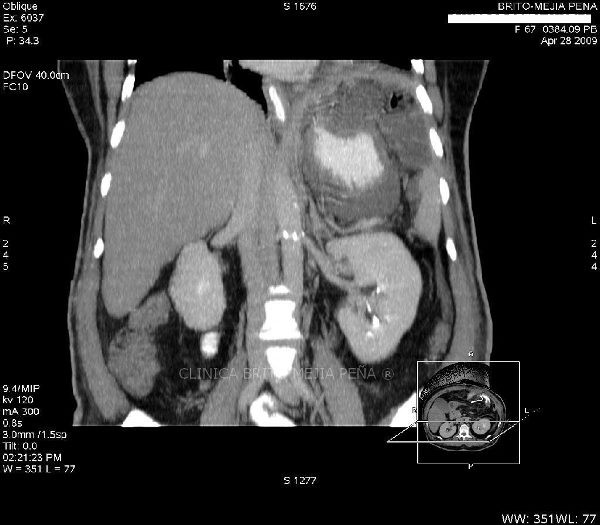

Hepatocarcinoma coronal